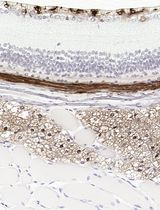

Malaria remains a serious healthcare problem in many countries across the tropical and sub-tropical regions (World Health Organization, 2019). As the parasite matures within the host’s erythrocyte, substantial changes happen to the architecture of the infected erythrocyte, giving rise to altered cytoadherence of the infected erythrocytes, which is believed to be an important player in pathogenesis of severe malaria (Craig et al., 2012). One of the cytoadherence characteristics of infected erythrocyte is the rosetting phenomenon, where a late-stage parasite-infected erythrocyte stably adheres to at least an uninfected erythrocyte (Figure 1). Since its discovery in the late 1980s (David et al., 1988), various methods have been used to visualize rosettes. Most of these methods are microscopy-based, using wet mount prepared with malaria-infected blood samples. These include unstained wet mount (Udomsangpetch et al., 1992), Giemsa-stained wet mount (Chotivanich et al., 1998; Lee et al., 2013 and 2014), and fluorescent dye Acridine Orange-stained wet mount (Udomsangpetch et al., 1989; Treutiger et al., 1998; Ribacke et al., 2013). These methods were easy to use and can be conducted even in less-equipped laboratories. Here, we have provided protocols for the three methods, along with the steps of sample preparation for these techniques. When done properly, these methods can be used interchangeably according to the resources available in the work place.

Figure 1. Pictures of a rosette taken 15s apart, Giemsa stained-wet mount method. Under wet mount condition, the cells are mobile, which helps to differentiate between rosettes and mere overlaps of cells. The Giemsa stain assists in visualizing the parasites. Scale bars: 10 µm.